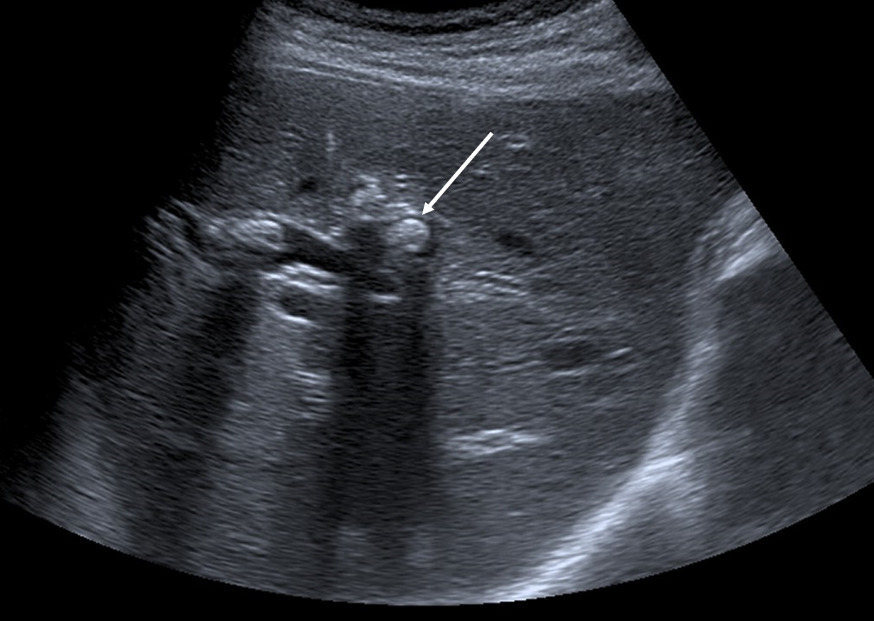

Échographie hépatique : examen clé du diagnostic

L’échographie hépatique est l’examen clé pour le diagnostic de syndrome LPAC. Celle-ci met typiquement en évidence les signes d’une microlithiase intrahépatique sous la forme d’images en « queue de comète » (échos de répétition liés à la vibration des microcristaux sous le faisceau d’ultrasons), de micro-­spots ou de « boue biliaire » (sludge) le long des canaux intrahépatiques (fig. 1A). Ces signes sont parfois difficilement identifiables, notamment en situation non sensibilisée et pour un opérateur non entraîné. Le principal diagnostic différentiel est représenté par les microhamartomes (ou complexes de von Meyenburg) qui peuvent parfois se présenter sous la forme d’artéfacts en queue de comète.9 Une échographie normale standard n’élimine pas le diag­nostic et il peut être nécessaire de répéter l’examen par un radiologue expérimenté et formé à la sémio­logie du syndrome LPAC. Moins fréquemment (5 à 10 % des cas), le syndrome LPAC peut se présenter sous la forme de vrais calculs (macrolithiases) intra- ou extrahépatiques (fig. 1B).4 Une lithiase vésiculaire n’est observée que chez un tiers des patients atteints de syndrome LPAC.